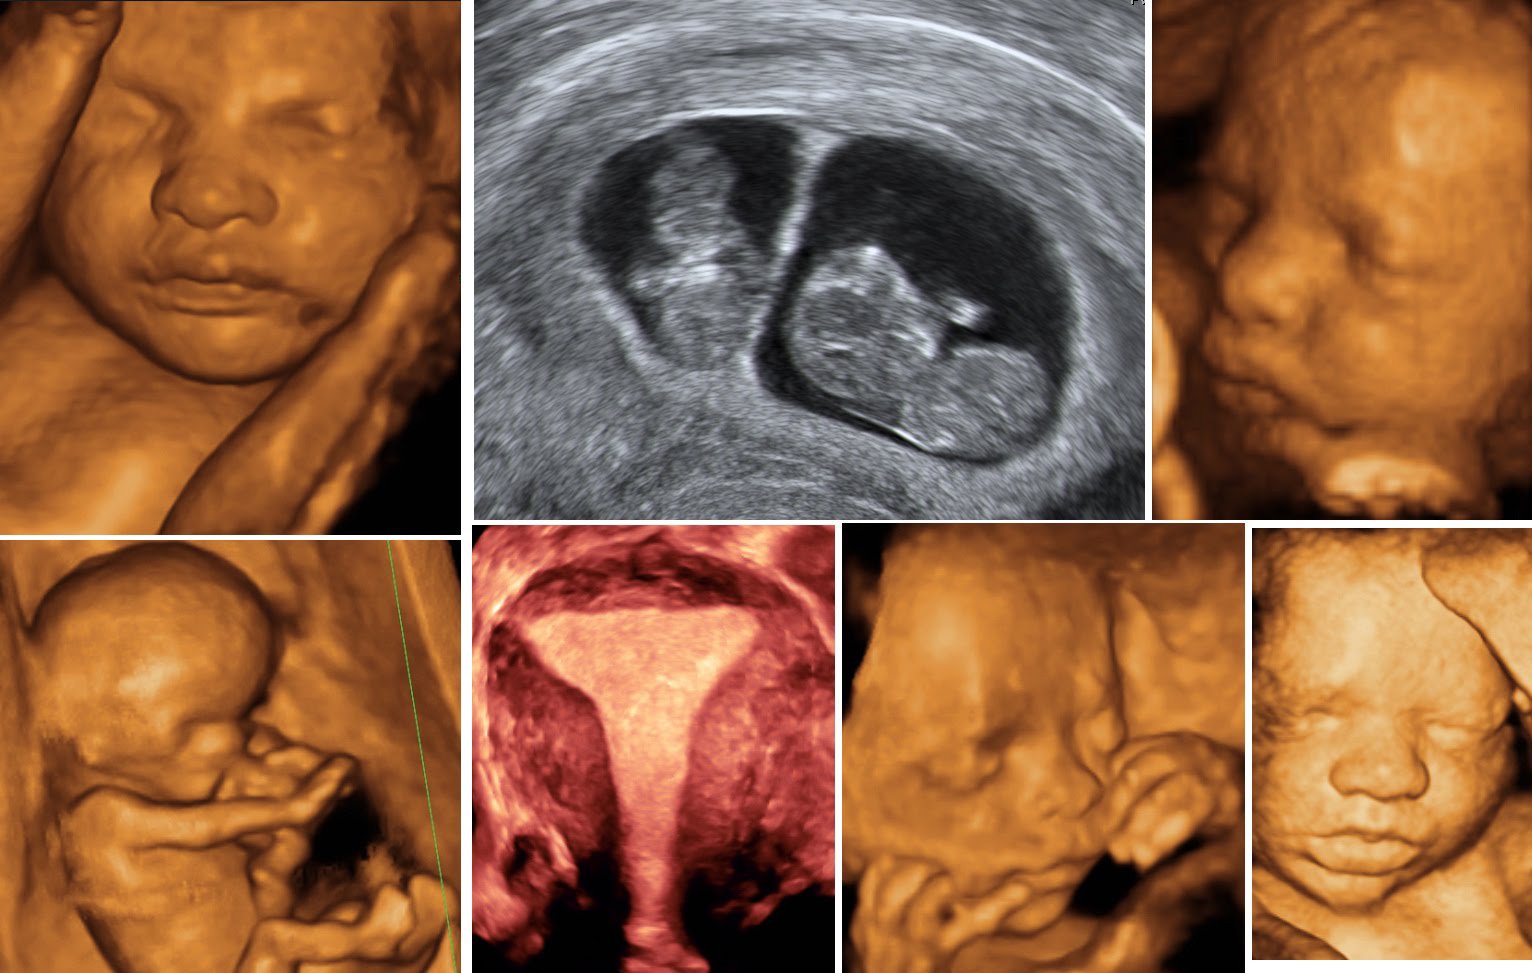

I visited Delta Imaging for a Color Doppler scan during my high-risk pregnancy. Dr. Krushna Gandhi was meticulous and kind, explaining the blood flow readings in detail. Her calm approach and expertise gave me so much confidence. Truly a doctor you can trust.

Delta Imaging Clinic gave us one of the most magical moments of our pregnancy. Dr. Gandhi explained everything so patiently during the 4D scan and made sure we were relaxed and informed. Highly recommend them to all expecting parents!

Seeing our baby’s face for the first time in 4D brought tears to our eyes. Dr. Krushna Gandhi made the whole experience so special and comforting. The images were crystal clear, and the staff at Delta Imaging Clinic were incredibly warm and professional. It’s a memory we’ll cherish forever.